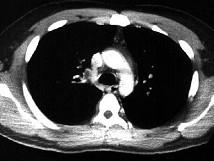

问题 男,28岁,突发呼吸困难,结合影像图像,选择最可能的诊断 ( )

选项 A、右肺中央肺癌并右上肺不张,淋巴转移 B、右上肺小叶性肺炎 C、右上肺奇叶 D、右主肺动脉栓塞 E、右上肺大叶性肺炎

答案 D